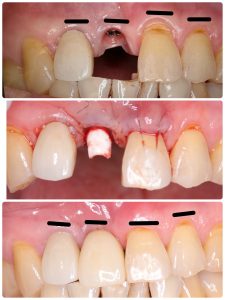

前歯オペから2ヶ月チョイで本日セット

リムーブし即再埋入、軟組織ボリューミーアップ

セメント固定からスクリュー固定変更